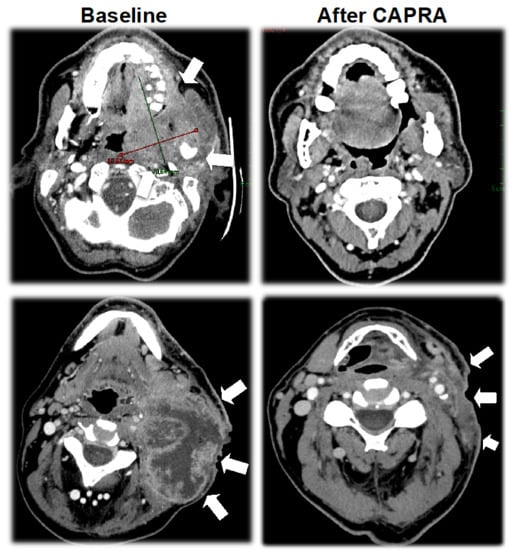

3.3. Activity